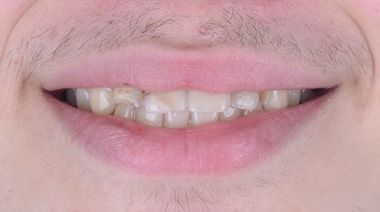

Firstly, we treated the gap between the teeth with Invisalign. We also corrected the angle of the front teeth. Invisalign Lite was enough. Glenn visited Turkey 4 times in a period of 8 months. During his last visit, we replaced the old fillings in his front teeth with composite bonding. We performed lingual retrainer to maintain the alignment of the teeth. We produced an sx plate for him to use at night and delivered it to him. Glenn was very happy. He said he wanted to study at a dentistry faculty.

Dr Berra performed my orthodontic treatment. I was comfortable with clear aligners, we thought it would look better than braces. Thank you very much to the Cure Voyage team and Dr Berra.